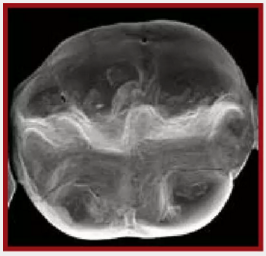

復(fù)合樹脂在即刻充填后,觀察其在電子顯微鏡下的掃描圖像,本次研究選擇了9種具有代表性的復(fù)合樹脂材料。

1.png

Clearfil Majesty Kuraray America 可樂麗